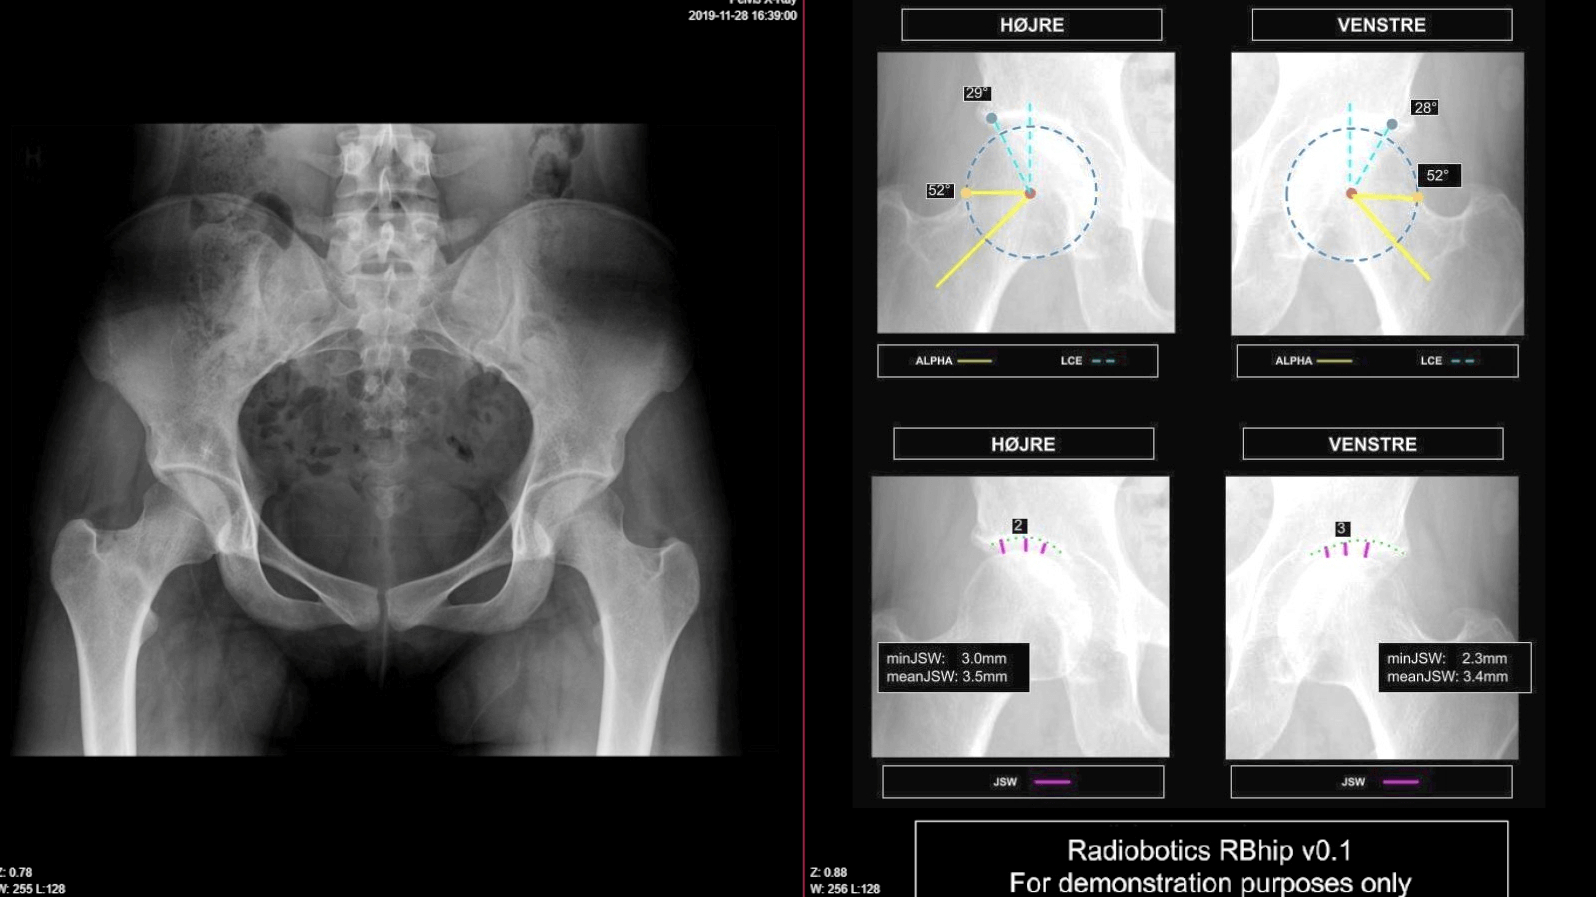

Kunstig intelligens sikrer hurtige og præcise svar på røntgenundersøgelser

Travlhed og mangel på ressourcer betyder, at der ofte er lange ventetider på at få svar på røntgenbilleder, samt en betydelig risiko for fejldiagnosticering. I de kommende år vil vi desuden opleve stor mangel på radiologer. Derfor har Radiobotics udviklet en algoritme, der er trænet til automatisk at kunne identificere sygdomme på nogle af de almindelige typer røntgenbilleder, som tager størstedelen af radiologernes tid og ressourcer. Løsningen, der er baseret på kunstig intelligens, er med til at nedbringe ventetiderne, aflaste personalet på sygehusene og er forbundet med færre fejl i diagnosticeringen. Læs mere her.